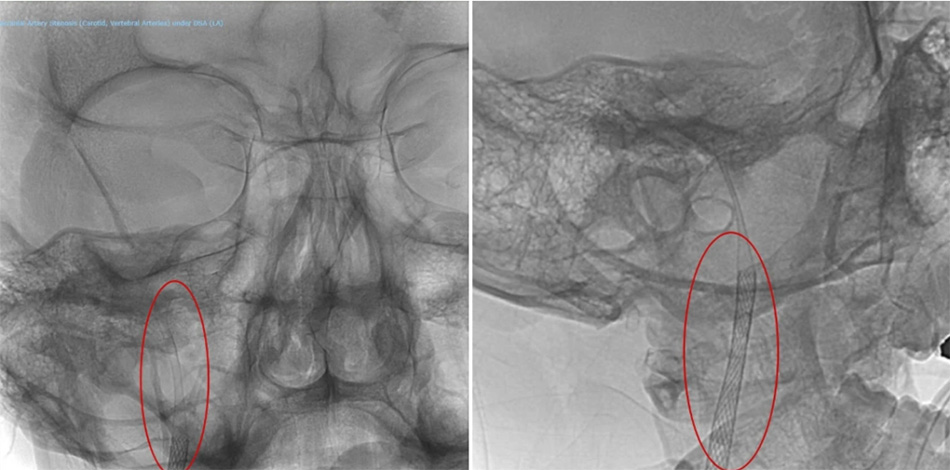

Before performing the procedure, Mr. A.M was fully informed by the doctor about his condition and the treatment method. Given the 80mm-long artery dissection, two overlapping stents were required to ensure the artery remained open and clear.

The procedure, led by Dr Duc and his team, was successfully completed within three hours in the Cathlab room, utilizing advanced equipment, including the multi-functional digital subtraction angiography (DSA) system. The system provides detailed imaging of coronary arteries, brain vessels, and the entire vascular system. Through a small incision in the thigh, the team inserted a catheter with a stent, carefully guiding it to the site of the tear in the artery. The stent was then deployed to “seal” the damaged area, restoring normal blood flow in the carotid artery.

The patient’s vascular image after the stent placement